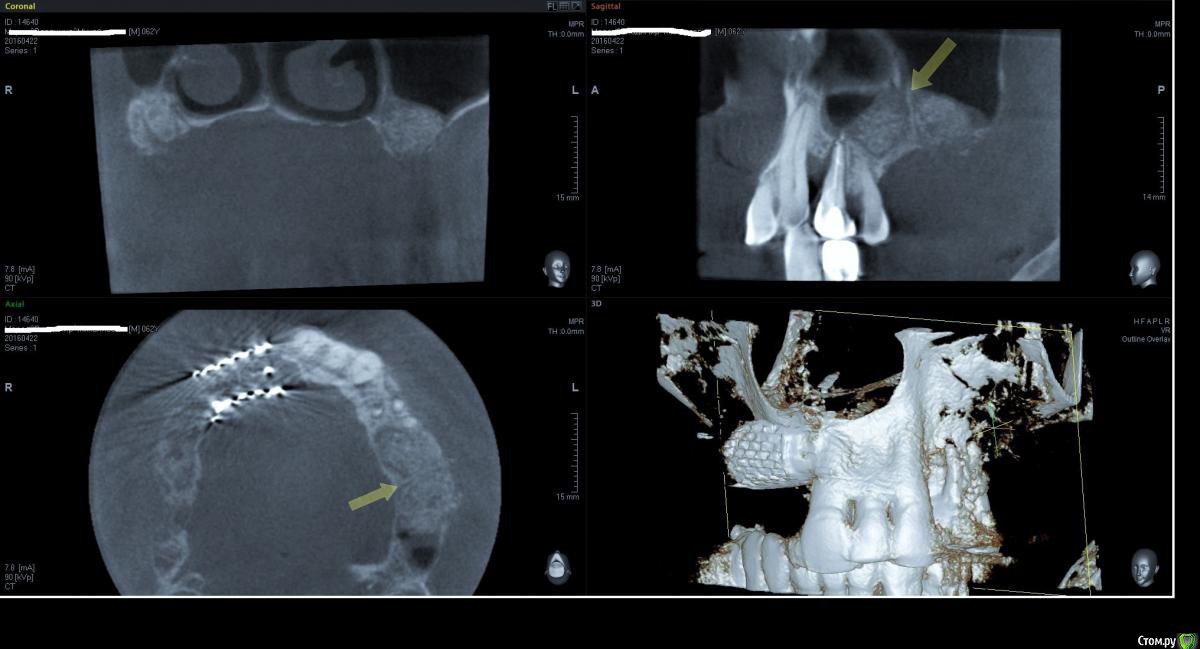

Kovalov Igor Опубликовано 19 мая, 2016 Поделиться Опубликовано 19 мая, 2016 (изменено) Здравствуйте уважаемые форумчане! Нужен совет по повторному синуслифтингу....3 месяца назад проводилась попытка синуслифтинга в 1 сегменте, отсутствие 14,15,16 зубов ... Разрез, формирование окна, в этом случае выбрал вход в синус с двух окон в проекции 14 и 16, получить перфу возле септы в области 16 когда отслаивал ... 14 отслойка без проблем... закрыл окна мембраной и ушил отправил погулять на 2,5-3 месяца.Вопрос как поступить ? Сделать одно большое окно? Как быть со спайками и как сложно их отделять ? Мембрану под перфу не подложил так как не делал ниразу этого... Кт после 3х месяцев ... Изменено 19 мая, 2016 пользователем Kovalov Igor Ссылка на комментарий

kriokov Опубликовано 19 мая, 2016 Поделиться Опубликовано 19 мая, 2016 пошел бы стандартно одним окном, да и первый раз думаю надо было одним окном идти, там не полная септа.Иногда приходиться остро работать на спайках как при расщеплении. Не знаю, но мне здесь одно здоровое окно видиться. И наверное зря Вы септу не спилили или не выкусили при первом заходе, если решили через три мес на повторный идти. Синус не плохо выглядит, думаю нормально все будет. 6 Ссылка на комментарий

red_butler Опубликовано 21 мая, 2016 Поделиться Опубликовано 21 мая, 2016 Куда вы 2гр L сыпите та? Тромбуете штоль?Даже еще раз пересмотрел срезы, Вы считаете что на такой операционной площади и при таком строении синуса расход будет меньше? 3 Ссылка на комментарий

Kovalov Igor Опубликовано 21 мая, 2016 Автор Поделиться Опубликовано 21 мая, 2016 Даже еще раз пересмотрел срезы, Вы считаете что на такой операционной площади и при таком строении синуса расход будет меньше?Ушло 2 грамма вы правы! ))) Спасибо всем за советы , ошибки были в первом случае малое и высоко расположенное окно, сделал в этот раз одно большое окно, спайки были только по периметру окна , было ощущение что окно начало заростать костью через три месяца, будто пластинка была поверх мембраны , может показалось ...Отслаивал до септы, графт 1,5 гр. в синус и 0,5 латерально от винтов и укрыл мембраной 25*25 владмива, мембрана не понравилась если честно ) Ссылка на комментарий